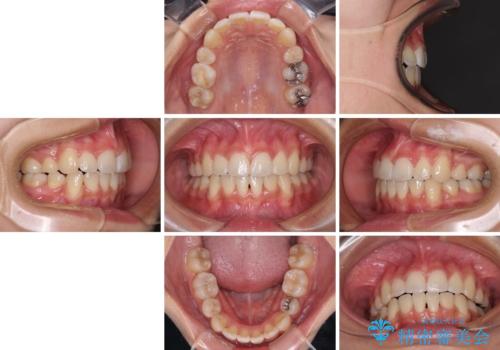

- 上下前歯のデコボコと、それによる磨きづらさを気にして来院された患者様です。

叢生解消のため、上下左右第一小臼歯4本を抜歯し、ワイヤー装置にて矯正治療を行うこととしました。

半年ほどで前歯のデコボコは改善され、汚れの溜まりやすさは解消されました。

抜歯スペースを閉じるために期間がかかりましたが、当初予定通り2年強で終えることができました。